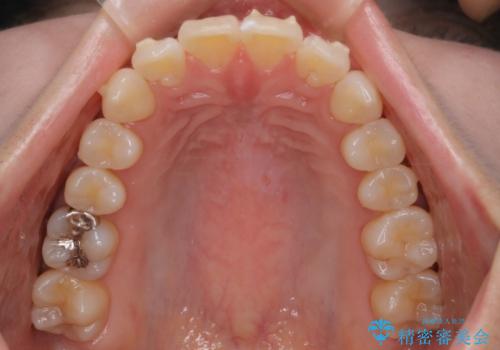

- インビザラインで非抜歯治療を行いました。IPRと拡大をし、叢生、咬合をきれいにしました。

主訴であったかみ合わせを正しい位置に動かし、バランスよくかめるようになりました。矯正治療終了後にメタルインレーをセラミックインレーに替えました。